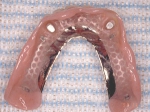

義歯の裏側

義歯の内面(内側に赤いプラスチックが見えますがこれが消耗品で半年に一度くらい交換すれば元の維持が復活します。)

義歯の内面